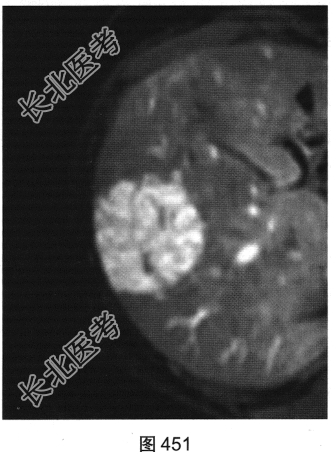

- 多项选择题3.[提示]随后患者接受上腹部MRI检查,如图449~图452所示。对患者MRI检查图像描述不正确的是( )

A、纤维瘢痕呈延迟强化

B、门静脉期病灶轻度强化

C、T1WI示病灶为稍低信号

D、动脉期病灶明显强化

E、T2WI示病灶为稍高信号

F、病灶内无纤维瘢痕